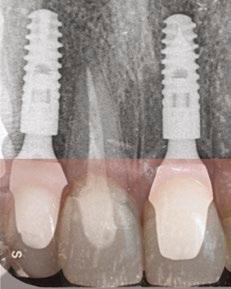

Imediátní implantace po extrakci

Okamžité zatížení implantátu